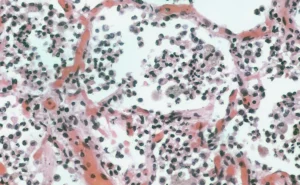

Метатуберкулезные изменения в легких возникают в результате замещения органа соединительной тканью. Часто они не имеют клинических симптомов и поэтому обнаруживаются при рентгенологическом исследовании. Чтобы выяснить причину изменений, необходимо пройти обследование у фтизиатра, после чего специалист подберет соответствующую тактику лечения, чтобы не допустить развития дыхательной недостаточности. Что это такое? Метатуберкулиновые поражения в легких — это заболевание, …